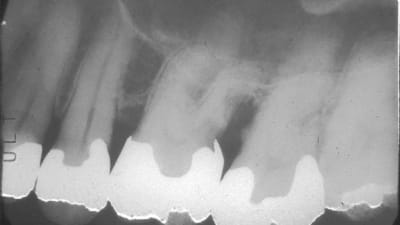

Special Report General Dentistry Digital Imaging Digital Radiography in General Practice: Is It Time to Convert? By Claudio M. Levato, DDS August 01, 2013 9 min read

Special Report Carestream Dental: Innovative Imaging Solutions Benefiting Patients and Practices August 01, 2013 4 min read

Special Report XDR Radiology: Digital Solutions Designed by Dentists for Dentists August 01, 2013 4 min read